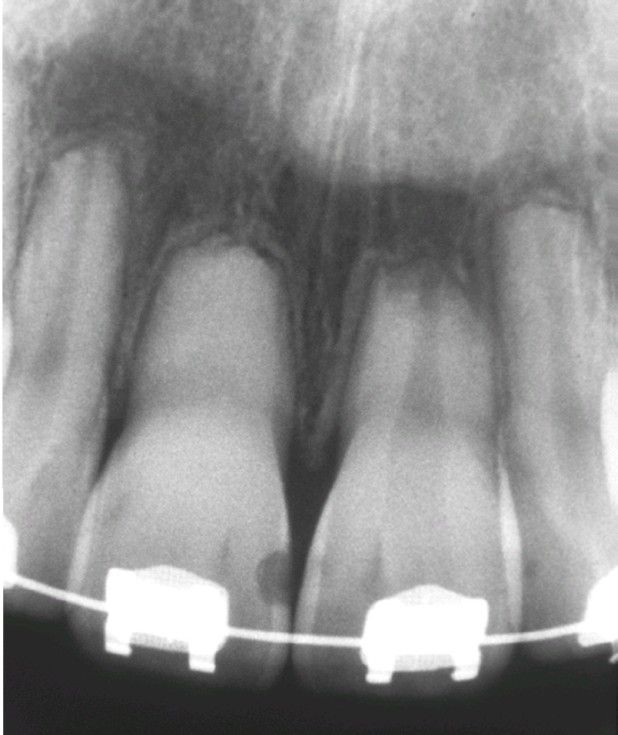

External resorption

Diffuse external resorption of radicular dentin of maxillary dentition. This process arose after initiation of orthodontics.